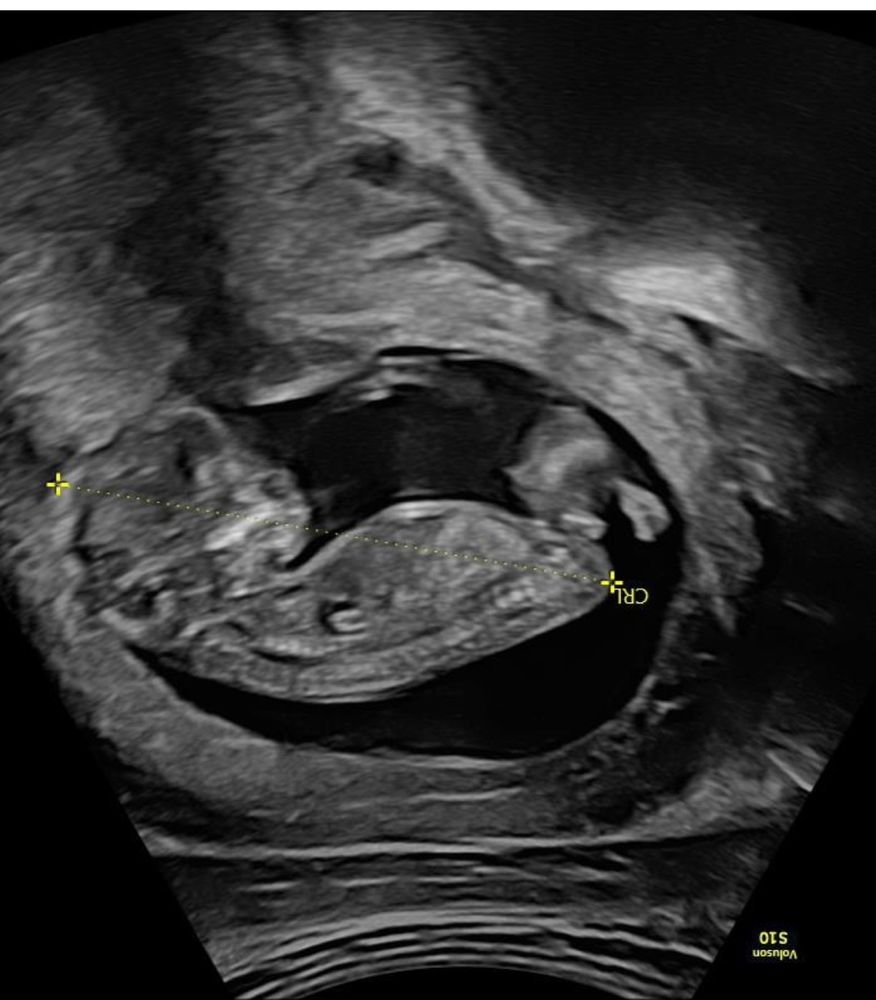

Вроде девочка по расположению полового бугорка. Но это не факт, конечно